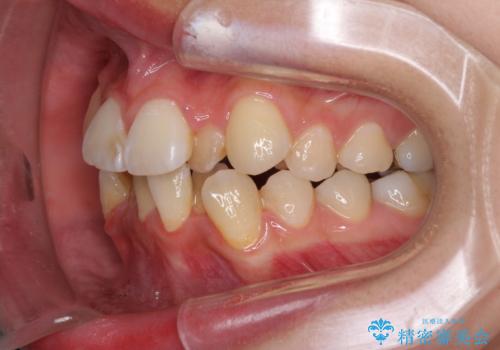

- 上下前歯のデコボコと、それによる磨きづらさを気にして来院された患者様です。

叢生解消のため、上下左右第一小臼歯4本を抜歯し、ワイヤー装置にて矯正治療を行うこととしました。

半年ほどで前歯のデコボコは改善され、汚れの溜まりやすさは解消されました。

抜歯スペースを閉じるために期間がかかりましたが、当初予定通り2年強で終えることができました。